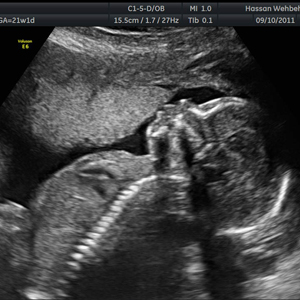

You have passed your first trimester milestone! Must read Here are Second Trimester Ultrasound Scans: Everything You Need To Know.

Home Second Trimester Ultrasound Scans: Everything You Need To Know Second Trimester Ultrasound Scans: Everything You Need To Know